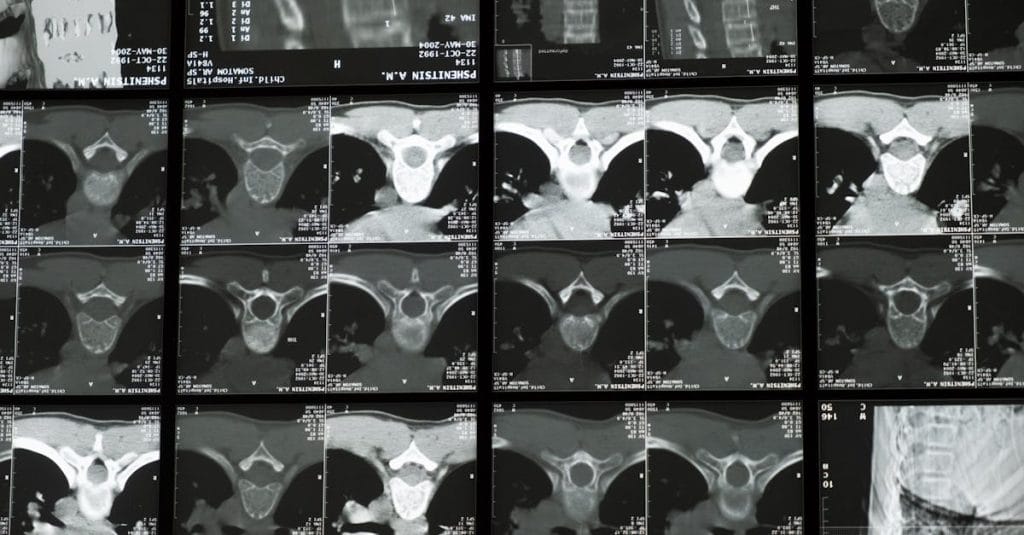

La décompression neurovertébrale est une technique qui consiste à appliquer une force de traction contrôlée sur la colonne vertébrale. Cette méthode vise à réaligner et à soulager la pression exercée sur les disques intervertébraux, permettant une meilleure circulation sanguine et un apport nutritionnel aux tissus environnants. Cela se traduit par une réduction des douleurs et une amélioration des fonctions corporelles.